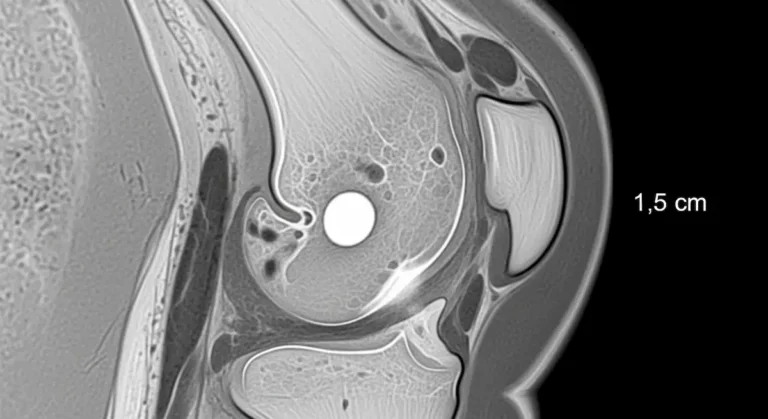

Osteocondrite dissecante: guia claro para entender e tratar

A osteocondrite dissecante é um problema que compromete a cartilagem e o osso logo abaixo dela. Surge com mais frequência…